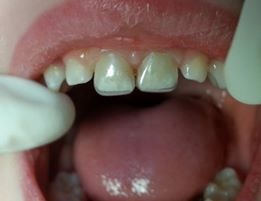

Leigh was 3 years old when he first came to my office with failed restorations and rampant caries (Figure 1). He had come from overseas where both he and his mother had bad experiences with dentists and developed severe dental-phobia. His mother was delighted to see that her children did not scream during treatment in our office.

A strip crown technique using ACTIVA BioACTIVE-RESTORATIVE requires fewer steps, takes less time, provides a better seal against secondary caries, and provides a more durable and fracture-resistant restoration. First I trim and pre-fit Nowak strip crowns so they are even with the sulcus (Figure 2). Because the prep in these cases is usually quite minimal, I typically do not need local anesthetic. I prep the teeth with a #4 or #6 round bur, slowly removing decay with short light touches. Incisal reduction is usually unnecessary, and I avoid it whenever possible. If needed, I use a very fine diamond to refine, shape and open contacts. I only work 2-3 seconds at a time and keep a 2×2 gauze under the teeth for children who are uncomfortable with the water spray and suction. Figure 3 shows the final prep.